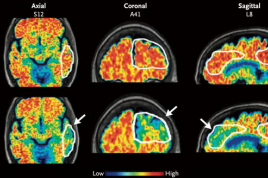

ألزهايمر

يمكن للاختبارات أن توفر نتائج في وقت أسرع بكثير من ثم الإسراع في تقديم أدوية جديدة لهذا المرض

قد يسبب هذا النوع من المرض الارتباك والضيق للمصابين وأحبائهم، لكن التكنولوجيا الحديثة يمكن أن توفر لهم فرصة حقيقية للاستمتاع بحياة أفضل